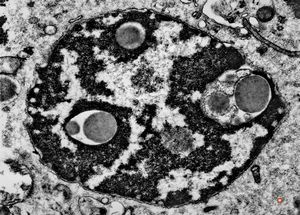

F,21y. | bone marrow - mastocytosis